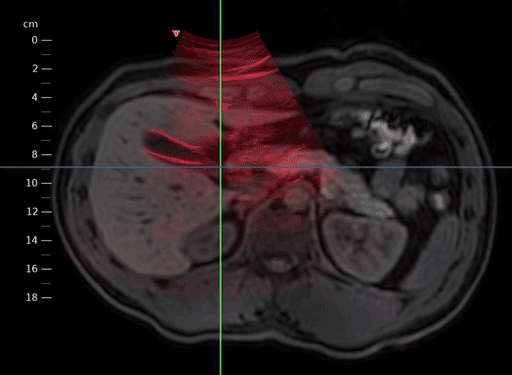

Furthermore, we can activate Color Blending for improved visualization by clicking on an empty space in a view (1) and selecting Blending > Color Blending (2).

../../_images/US.UltrasoundRegistrationTutorial.analysis02.png

Activation of color blending.

Through scrolling and blending, we can assess the alignment of the ultrasound sweep with the MR volume.

../../_images/US.UltrasoundRegistrationTutorial.analysis03.gif

Registered MR volume blended with the ultrasound sweep.